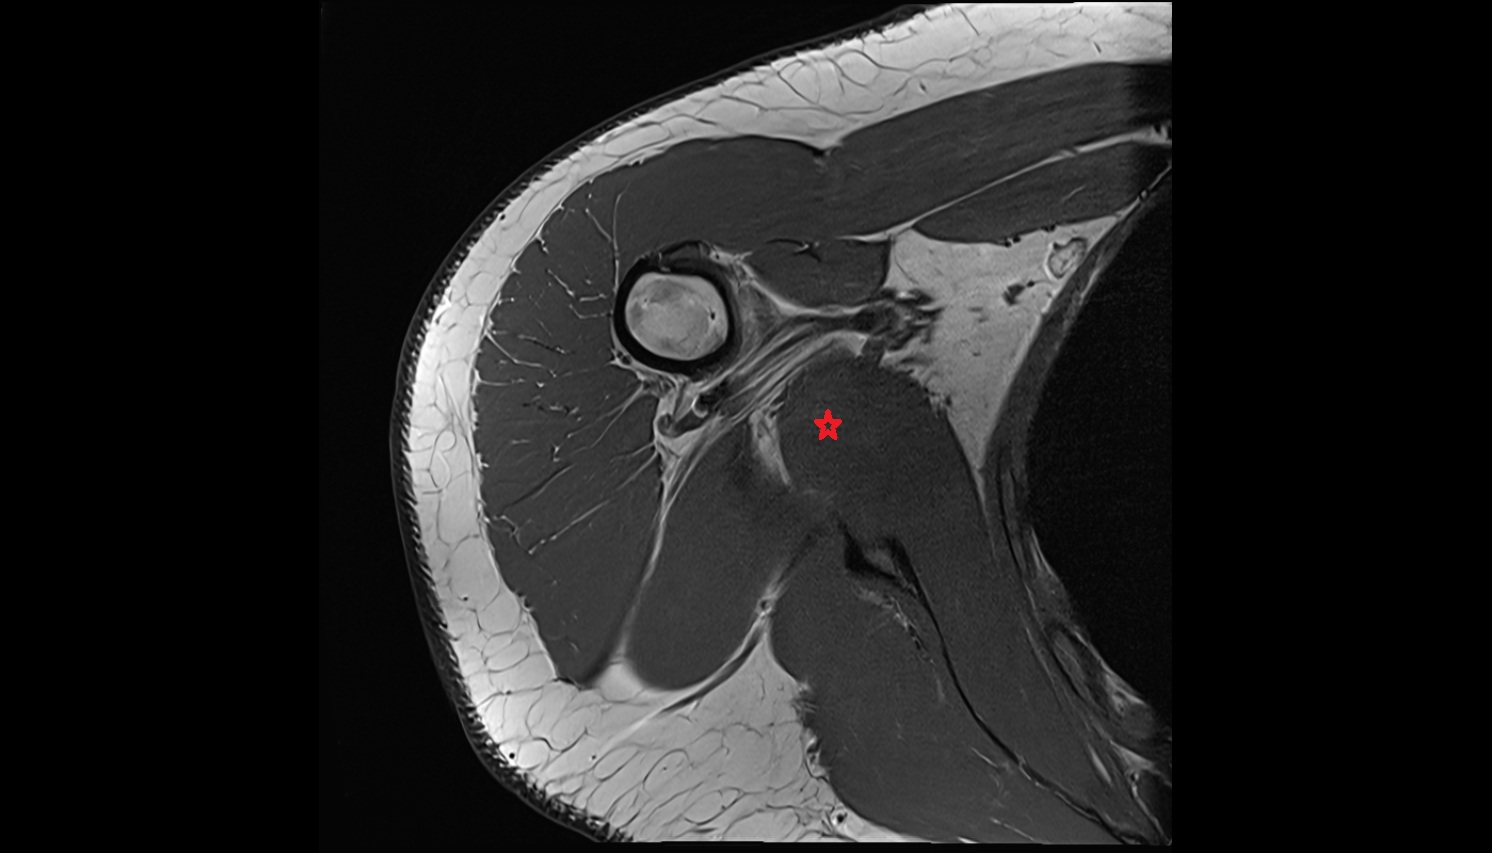

- Shoulder joint (glenohumeral joint)